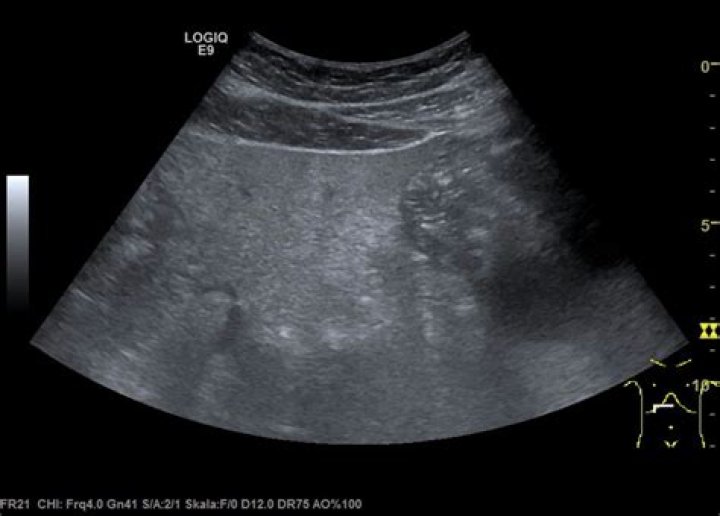

Does pancreatitis show up on ultrasound?

The ultrasound probe uses sound waves to produce images of the body that appear on a computer monitor. Your doctor can detect gallstones or signs of chronic pancreatitis, such as damage to the pancreatic tissue, with this test.

How does pancreatitis appear on ultrasound?

Sonographic findings of acute pancreatitis can be subtle and can include changes in pancreatic echogenicity, glandular enlargement, pancreatic duct dilation, and peripancreatic fluid [11]. Enlargement of the pancreas as well as hypoechoic or heterogeneous echotexture [8] is caused by associated interstitial edema (Fig.

How to diagnose pancreatitis with the help of ultrasound